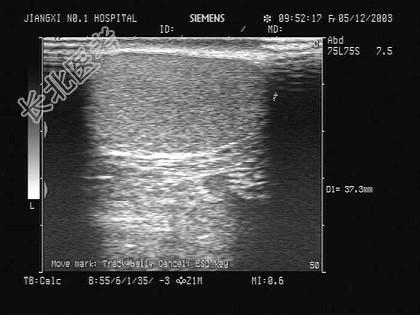

- 单项选择题该图为睾丸声像图,以下最可能的诊断为 ( )

A、睾丸肿瘤

B、正常回声

C、慢性睾丸炎

D、睾丸扭转

E、急性睾丸炎